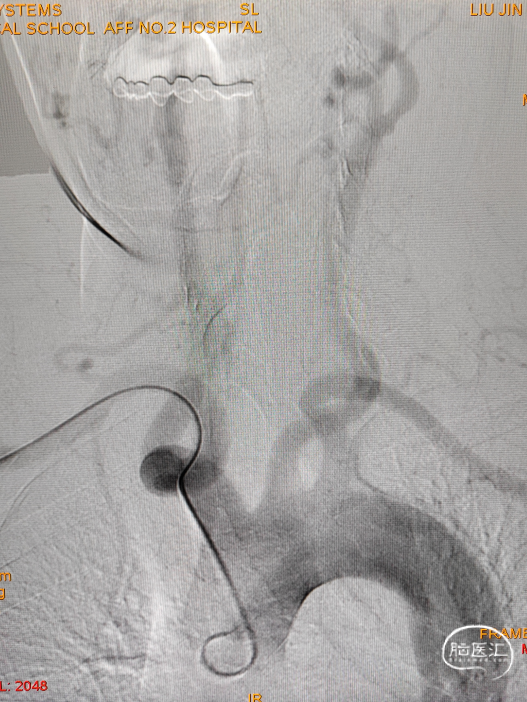

经桡入路造影

椎动脉后循环旋转造影

造影示:右侧优势椎,经右侧椎动脉导弯造影,双侧胚胎型大脑后动脉。

术前DSA:双侧后交通动脉开放。

R-CCA

L-CCA

R-VA

L-SUB-VA

6F 90cm 长鞘+5F 115cm 通桥银蛇®颅内支持导管建立通路。

0.014in*200cm 微导丝超选,球扩支架 2.5*8mm到位。

充盈球囊支架释放。

术后造影:基底动脉狭窄消失,双侧AICA通畅。